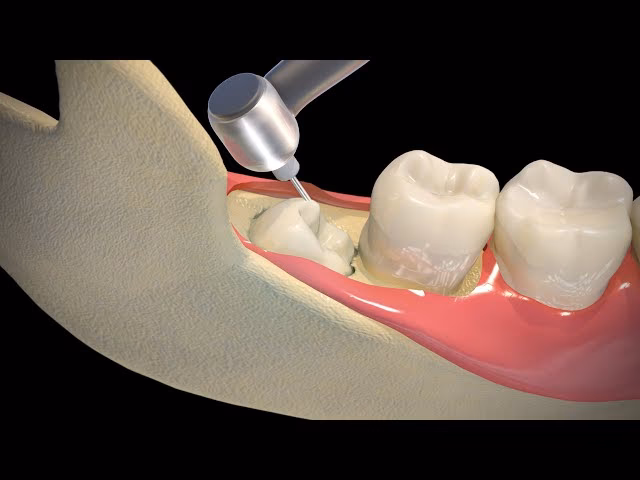

- Snit i tandkødet: Kirurgen lægger et lille snit i tandkødet for at få adgang til visdomstanden og den omkringliggende knogle.

- Fjernelse af knogle: Hvis tanden er dækket af kæbeknogle, vil kirurgen bruge et specielt bor til forsigtigt at fjerne den knogle, der blokerer adgangen.

- Deling af tanden: For at gøre fjernelsen lettere, især hvis tanden sidder fast, kan den blive delt i mindre stykker.

- Fjernelse af tanden: Tanden (eller stykkerne) fjernes forsigtigt fra kæben.

- Rensning og syning: Området renses for eventuelle rester af tand eller knogle. Såret lukkes med sting, som oftest er selvopløselige og forsvinder efter en uges tid.